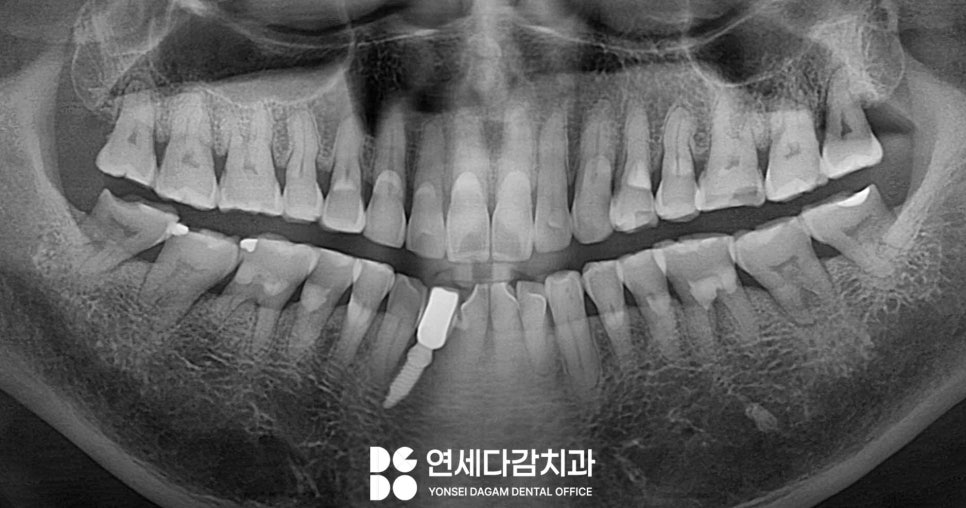

치아 교모증 특징

교모는 주로 어금니 부위에서

심하게 나타납니다.

음식을 분쇄하는 역할을 하는 어금니의

울퉁불퉁한 법랑질 표면이

편평하게 마모되어

문정역 치과 에서 표시한 부위처럼

내부 상아질이 비치는 것을

볼 수 있습니다.

외부 자극에 민감한 상아질에

가까워질수록 차가운 음식이나

공기에 시린 증상을 느끼게 됩니다.

정상적인 치아는 저작면에

울퉁불퉁한 교두가 있어

음식물을 잘 분쇄할 수 있으나,

교모가 진행되면 이런 구조가 없어져

평평하고 매끄러운 면이 되어

맞물림이 불균형하게 됩니다.

전체적으로 편평한 모습

그럼 저작능력이 저하되어

턱관절에 부담을 주기도 합니다.